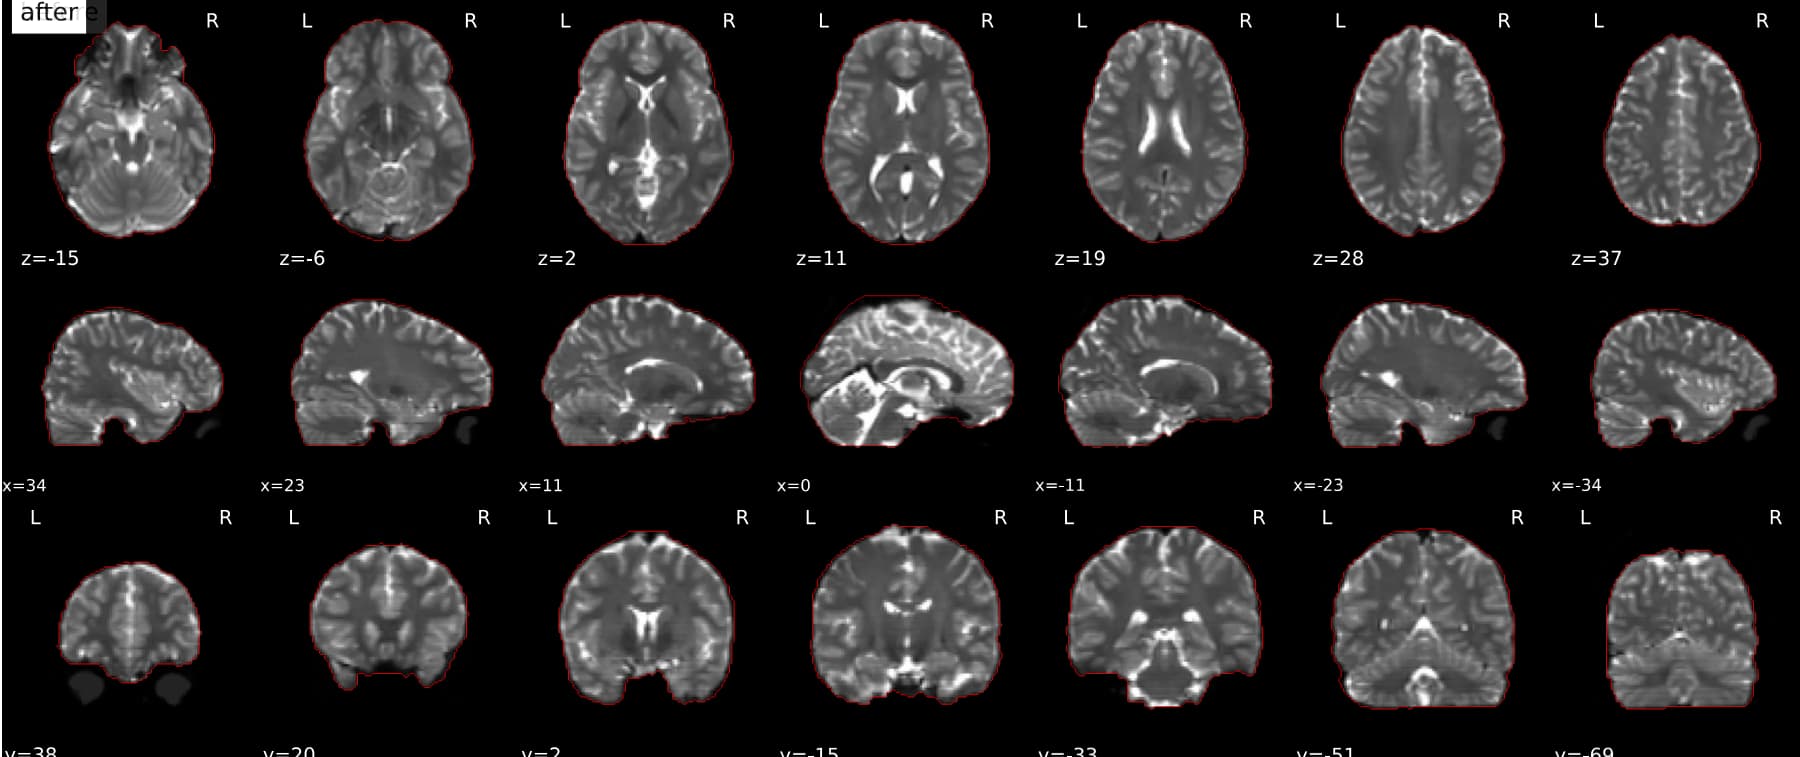

Should the masked (skull-stripped) B0 reference image be used in the alignment of the reference EPI image to the anatomical reference (coregistration)? The gif in the .html output shows a non-masked B0 image (eyeballs can be seen), even though the gif in the B=0 Reference Image step shows good masking. I also do not see the blue and cyan indicators in the b=0 reference gif, nor the red contour in the coregistration gif.